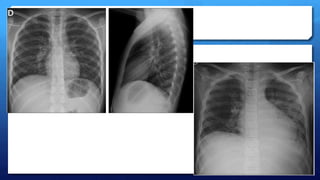

Evaluación radiológica:

 Confirmación del diagnóstico de neumonía

 Neumonía viral

 Hiperaireación o atrapamiento aéreo

 Infiltrados intersticiales de distribución difusa o parahiliar

 Engrosamiento peribronquial (manguitos)

 Atelectasias o microatelectasias especialmente en LSD y LM.

 < f  efusión pleural  peq. y no progresiva (Evidencia III)